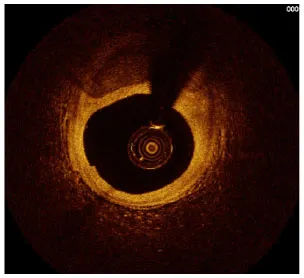

Moreover, the clinical-epidemiological features and lack of non-invasive specific diagnostic indicators, especially for microcalcification, are not well understood. VC especially coronary artery calcification (CAC) significantly increases the difficulty of percutaneous coronary intervention (PCI), and preevaluation of CAC lesions has a critical impact on subsequent treatment. Many imaging technologies have evolved in recent years to aid in the evaluation of calcified lesions, therefore, reducing the danger of intervention and improving the prognosis of surgery. These testing approaches have their own set of pros and cons, which are briefly summarized in Table 1. The diagnosis of microcalcifications mainly relies on optical coherence tomography (OCT) and 18FU-CT, both of which are invasive and expensive (172). Therefore, there is an urgent need to find methods and molecular markers for the non-invasive identification of early microcalcifications and to lay the foundation for the development of effective drugs for the treatment of or stabilization of microcalcifications.

Table 1

| Imaging modalities | CT | Coronary angiography | IVUS | OCT |

|---|---|---|---|---|

| Representative images | ![]() | ![]() | ![]() | ![]() |

| Invasive | No | Yes | Yes | Yes |

| Max resolution | 0.4–0.6 mm | NA | 100–200 μm | 10–20 μm |

| Notable shortcomings | Inadequate spatial resolution for detecting microcalcifications | Low resolution | It cannot determine the depth of calcification. | Expensive and prevents visualization of deep calcium |

| Sensitivity | *** | * | *** | **** |

| Location determination | *** | * | *** | **** |

| Quantitative analysis | *** | * | ** | **** |

Comparison of different methods for the examination of calcified lesions.

*~**** symbol indicates detection sensitivity/ability.